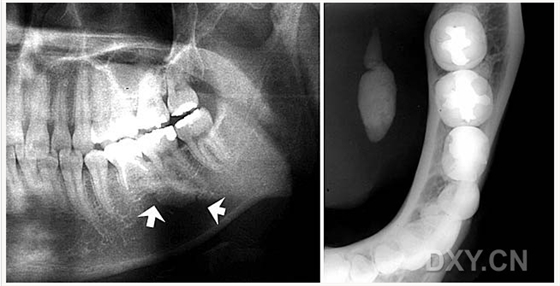

頜骨骨折